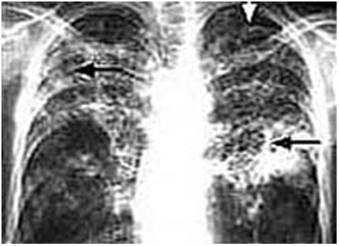

Khas : fibroinfiltrat di parahiller kiri, perselubungan homogen lobus superior segmen anterior Dx : Pneumonia segmen anterior lobus superior dextra dg BrPn sinistra Dx.

Murine Tissue‐Resident PDGFRα+ Fibro‐Adipogenic Progenitors Spontaneously Acquire Osteogenic Phenotype in an Altered Inflammatory Environment Journal of Bone and. Fibro Hints, Tips & Techniques from Dr. Pulmonary infiltrates with eosinophilia (PIE), also called eosinophilic pneumonia, is a syndrome associated with a variety of clinical entities, only some of which have an.